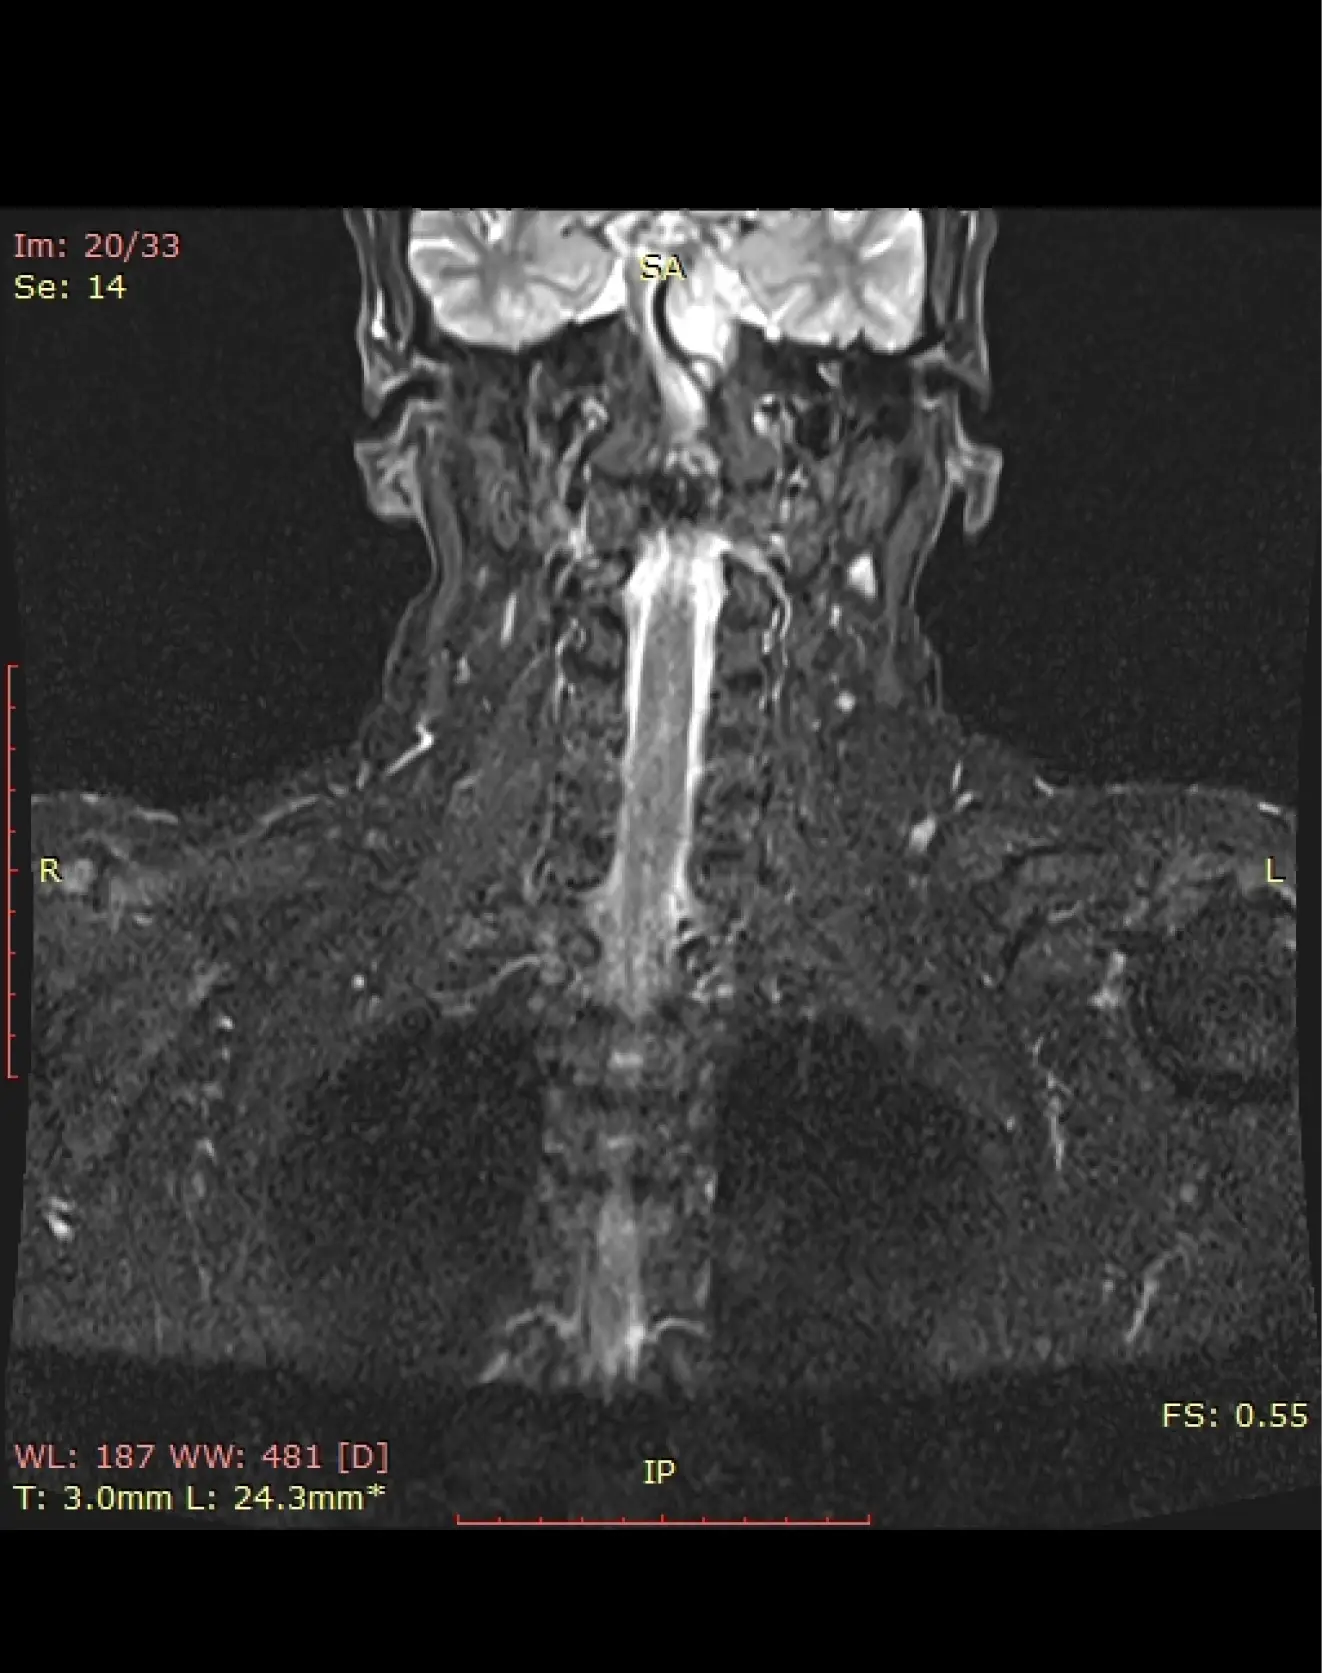

МРТ мягких тканей шеи + щитовидная железа

Визуализация слюнных желез, лимфатических узлов, щитовидной железы, воздушный просвет носоглотки, гортани, видимых отделов трахеи.